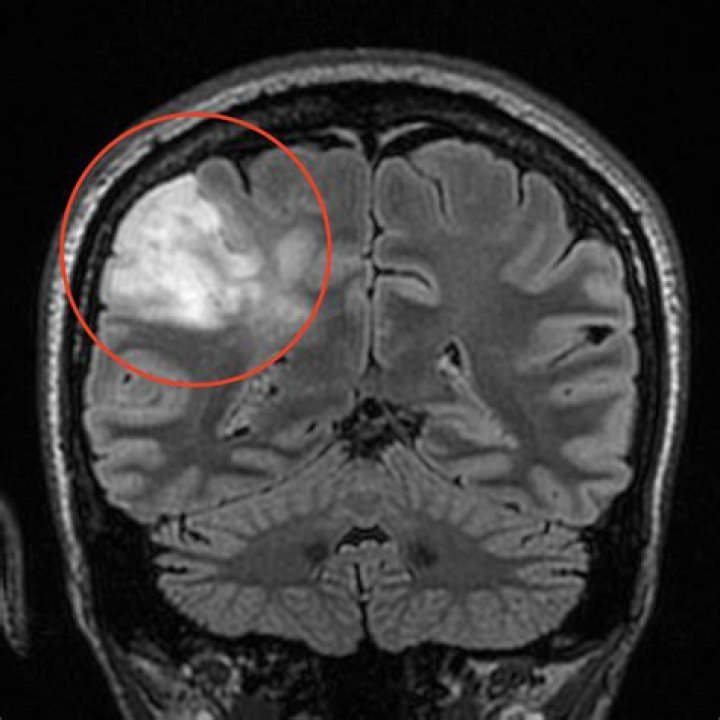

Oligodendrogliomas are commonly found in the white matter and the outer layer of the brain, called the cortex, but can form anywhere in the CNS. These tumors are called oligodendrogliomas because the cells resemble oligodendrocytes, a type of brain cell that supports and insulates nerve fibers in the CNS.

Oligodendroglioma is a primary central nervous system (CNS) tumor. This means it begins in the brain or spinal cord. To get an accurate diagnosis, a piece of tumor tissue will be removed during surgery, if possible.